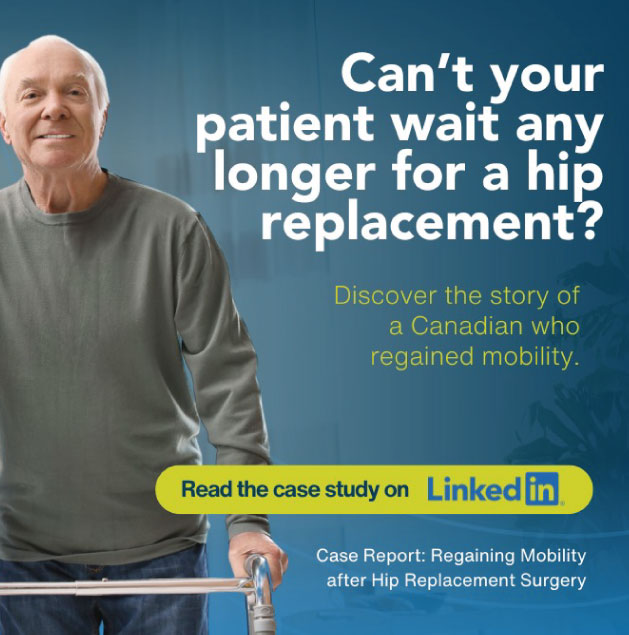

El movimiento es calidad de vida

Liderando la atención de trauma complejo con un enfoque multidisciplinario en Los Cabos

Este es tu momento para volver a vivir activo.